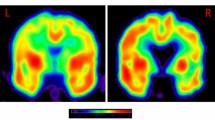

Long-lasting effects of 17β-estradiol on neuronal survival and learning and memory at 6 months after BCCAO

In the final set of experiments, we sought to determine whether animals treated with E2 during the first 3 m of BCCAO would still have beneficial effects on neuronal survival and cognitive function when examined at 6 months (6 m) after BCCAO. To examine neuronal survival and apoptosis in the hippocampal CA1 region, we used immunofluorescence staining for the neuronal marker, NeuN (green) and TUNEL analysis (red), respectively. Representative photomicrographs from all groups are displayed in Fig. 6a and the quantitative analysis is shown in Fig. 6b. The results demonstrate that BCCAO 6 m caused a significant decrease in neuronal survival (number of NeuN + cells) and an increase in apoptotic cells (number of TUNEL + cells) in the hippocampal CA1 region, as compared to sham controls (Fig. 6a & b). E2 treatment during only the first 3 months of BCCAO showed lasting beneficial effects at 6 m BCCAO, as evidenced by enhanced neuronal survival and reduced apoptosis in the hippocampal CA1 region, as compared to the BCCAO 6 m placebo control (Fig. 6a & b). Additionally, as shown in Fig. 6c, ultrastructure analysis of CA1 pyramidal neuron showed an irregular contour and an altered pattern of nuclear chromatin distribution in BCCAO 6 m and Pla 6 m groups, as well as swollen mitochondria with broken cristae, and dilated cisternae of rough endoplasmic reticulum, all signs of neuronal damage. In contrast, hippocampal CA1 neurons in E2-treated animals showed generally normal morphological appearance for neuronal nuclei and cytopasmic organelles. We next examined the ability of E2 treatment for the first 3 m of BCCAO to preserve cognitive function at 6 m BCCAO. Cognitive function in animals from all groups was examined using the Morris Water Maze (MWM) test. Latency trials were carried out from days 1 to day 5 to examine spatial learning ability (Fig. 6d), while probe trials were carried out on days 3 and 5 to examine spatial memory (Fig. 6e). Representative tracings for the latency and probe trials are shown in Fig. 6f & g, respectively. As shown in Fig. 6d–g, 6m BCCAO animals displayed a significant longer time in latency to find the platform (Fig. 6d & f), and a significant shorter time spent in the platform quadrant (Fig. 6e & g), as compared to 6 m sham controls. Importantly, the animals with continuously E2-treatment for the first 3 m exhibited significant preservation of cognitive function at 6 m BCCAO, as evidenced by a significantly decreased latency to find the platform and a significantly increased time spent in the platform quadrant, compared to BCCAO vehicle controls (Fig. 6d–g).

(a) Representative photographs for NeuN (Green) and TUNEL (Red) staining; (b) Quantify for NeuN- or TUNEL-positive cells in per 250 μm length of the medial CA1 pyramidal cell layer. n = 4–5, Scale bar = 50 μm and magnification 40×; *P < 0.05 vs. sham 6 m group, #P < 0.05 vs. Pla 6 m group; (c) EM results show ultrastructure of CA1 neuron. N: nucleus; Mit: mitochondria; M: membrane. Latency trail (d) and Probe trail (e) in Morris water maze. *P < 0.05 vs. sham 6 m on the same day; #P < 0.05 vs. Pla 6 m group on the same day. n = 6. Representative tracks for Latency trail (f) (a-sham 6 m, b-Pla 6 m, c- E2 6 m) and Probe trail (G) (d-sham 6 m, e-Pla 6 m, f- E2 6 m).